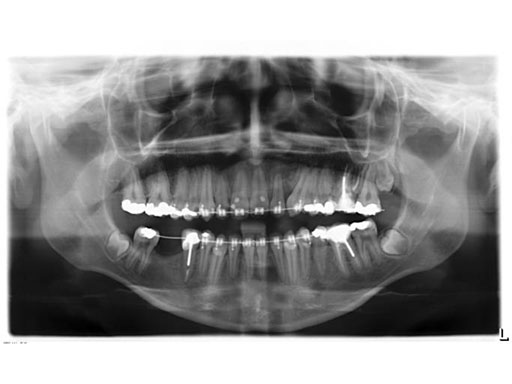

Lefort I maxillary osteotomy, bilateral sagittal osteotomies, and a genioplasty, all fixed with matrix orthognathic system used in a 19-year-old female with significant skeletofacial deformity including maxillary hypoplasia, mandibular excess, and laterognathia.

Fig 1a-c Preoperative images.